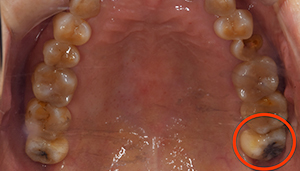

親知らずが虫歯になっている症例

- 抜歯前写真(レントゲン)

- 抜歯前の口腔内写真

- 抜歯した歯の写真

| 年齢 | 40代・男性 |

|---|---|

| 主訴 | 主訴:親知らずを抜きたい 治療部位:左下の親知らず |

| 親知らずの生え方 | 斜めに生えている |

| 抜歯時間 | 説明、麻酔等含めて約60分 |

| 費用 | 合計 約5,400円(保険診療3割負担) ■内訳 約1,900円 CT撮影約3,500円 (2025年2月現在) |

| 抜歯内容 | 左下8番の普通抜歯 |

| 治療方針 | 初診時に親知らずの虫歯を確認しました。 先に別の部位の治療をしていましたが、痛みが出てきたため抜歯を行うこととなりました。 |

| 特記事項 | 抜歯をする前にCTを撮影をし、下歯槽神経との位置を確認した上で抜歯を行いました。 |

| 担当者所見 | 初診のご来院時から、すでに虫歯が大きく進行していました。 ご来院時にお痛みはなかったものの、大きい虫歯でしたので、いつ痛みだしてもおかしくない状態でした。 麻酔が効きづらかったため抜歯に時間を要しましたが、根が折れることなく無事に抜けました。 |